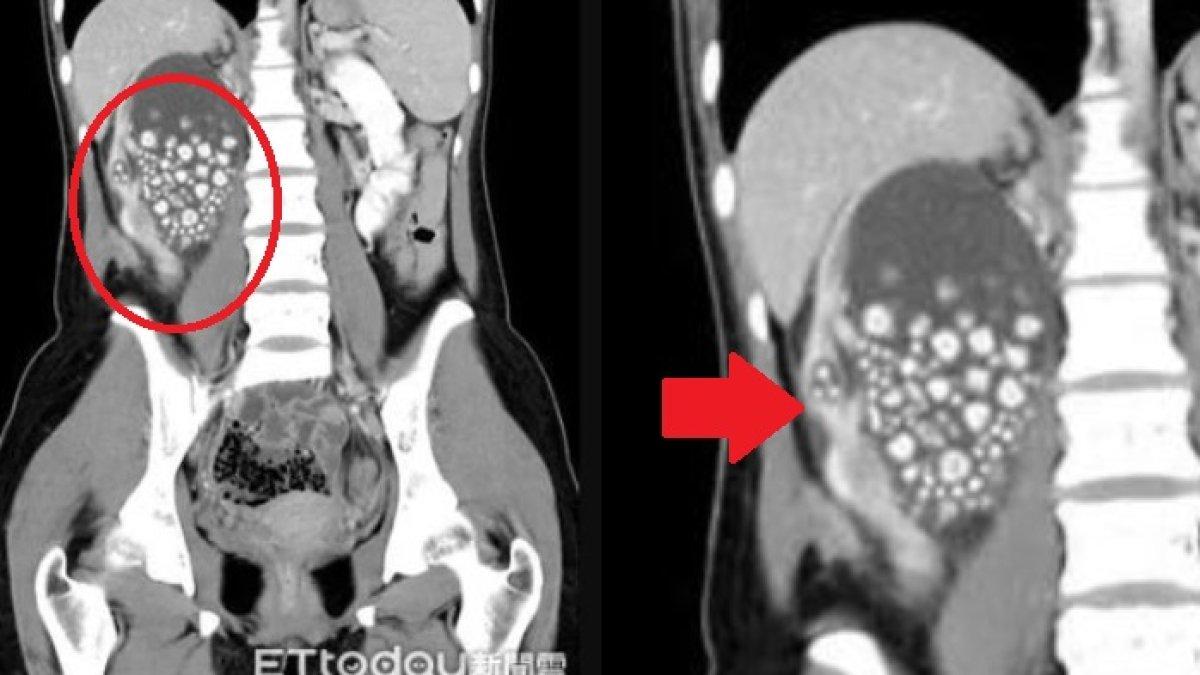

Lebih dari 300 batu ginjal berhasil diangkat dari seorang gadis berusia 20 tahun di Taiwan.

Mereka menemukan ginjalnya bengkak parah dengan ratusan batu di dalamnya yang tampak seperti ‘roti kukus kecil’.

CT scan menemukan bahwa batu tersebut berukuran antara 5mm dan 2cm.

CT scan menemukan bahwa batu tersebut berukuran antara 5mm dan 2cm (ETtoday)

Dokter melakukan operasi pada Xiao untuk menghilangkan batu tersebut di pusat Medis Chi Mei di kota Tainan di Taiwan.